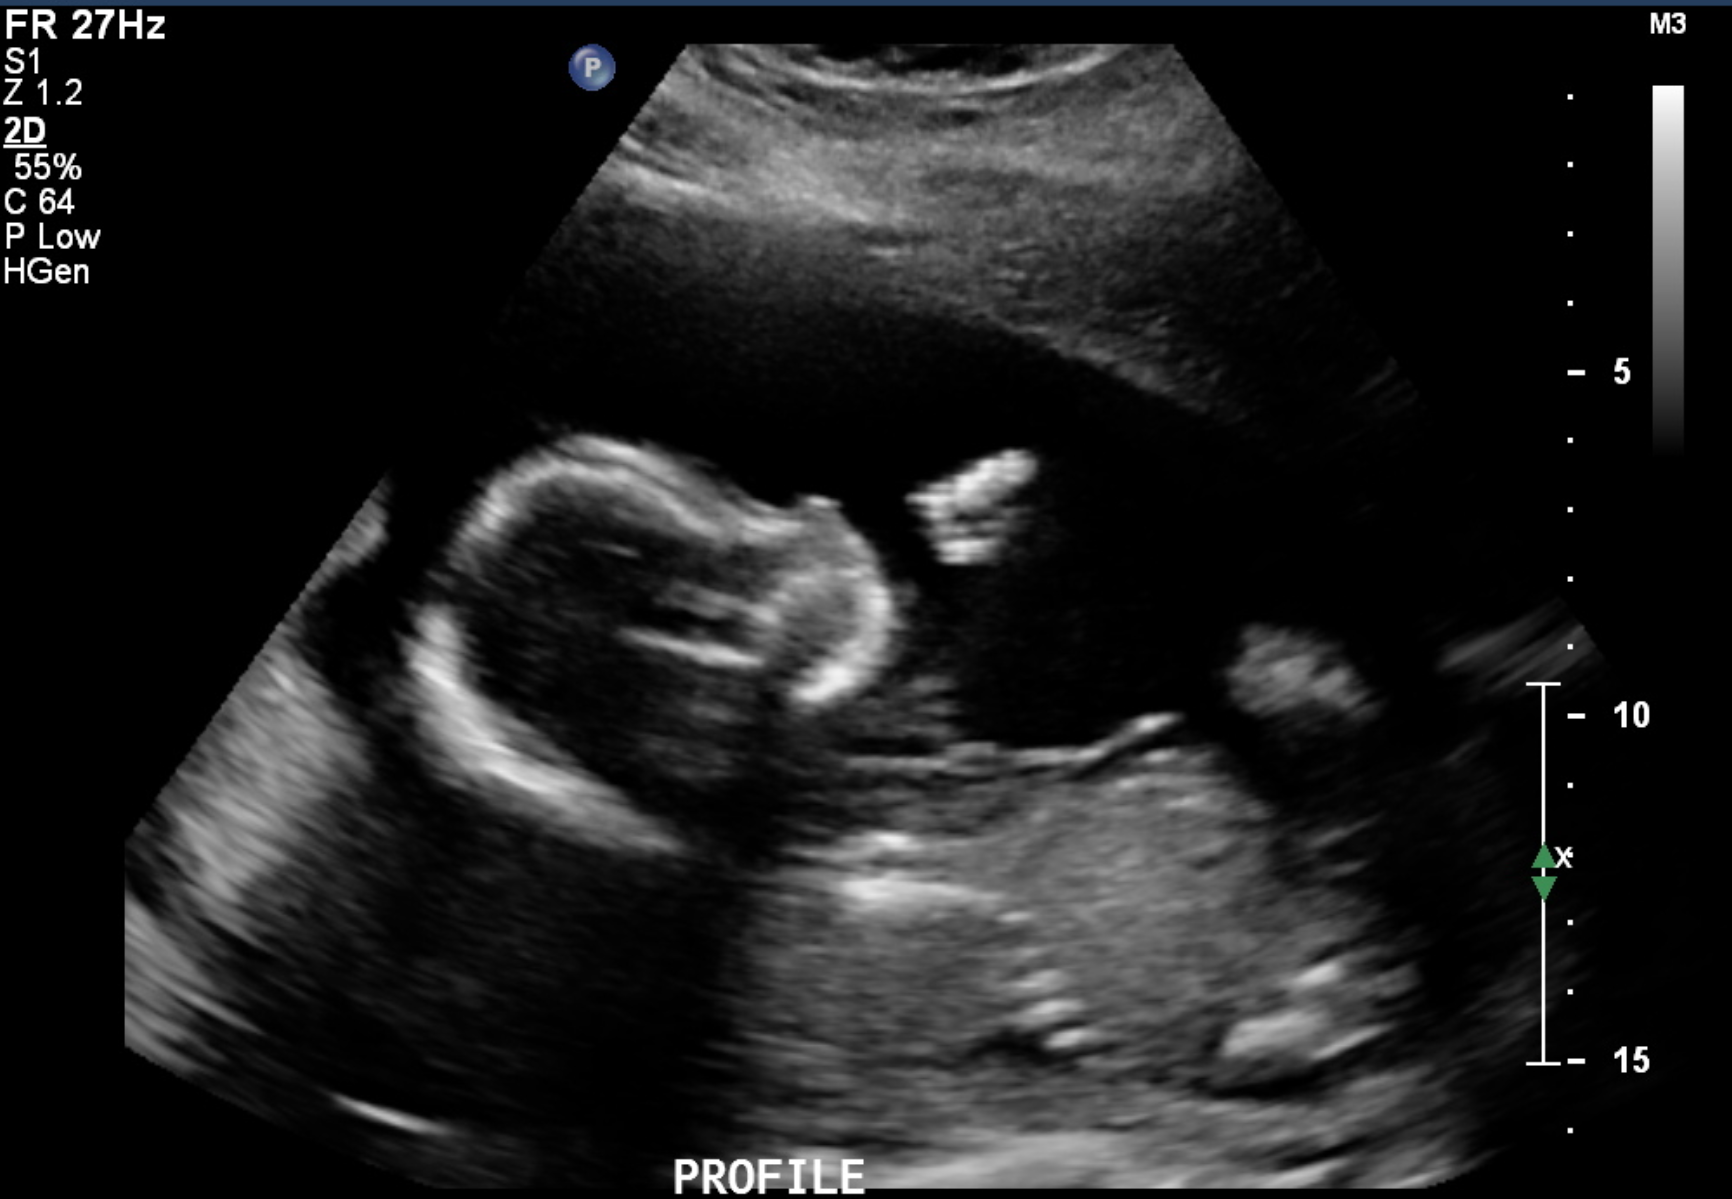

today we had our anatomy scan.... 19w! here's a little comparison between the NT Scan photo and today's Anatomy Scan photo!!! I love our little sweet pea so much!!!

here's a little comparison between the NT Scan photo and today's Anatomy Scan photo!!! I love our little sweet pea so much!!!